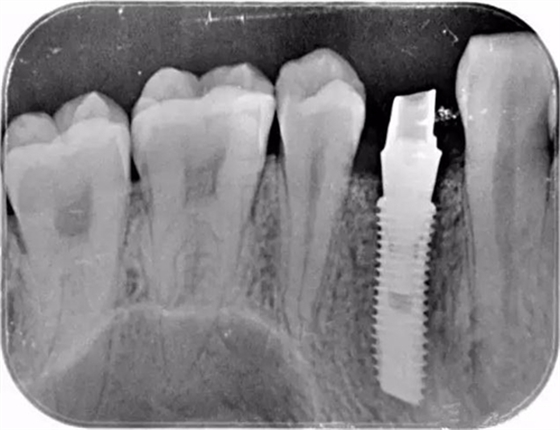

這個(gè)是顧客術(shù)后旋入成品基臺的X片

該顧客選擇的是登騰Superline種植體.因?yàn)轭櫩凸歉吖菍挆l件很好,選擇種植4.0*12植體植入。術(shù)中發(fā)現(xiàn)頰側(cè)骨壁存在缺損,植入Biooss骨粉,加固種植體。從照片中可以看到基臺愈合之后的效果不錯(cuò)。